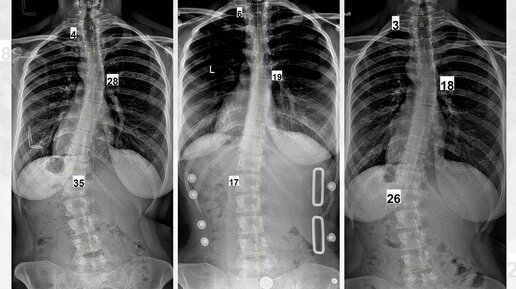

Лечение сколиоза, когда вам за 30

В мире нет доказанных методов лечения сколиоза у взрослых. С появлением корсета Шено все меньшее количество взрослых имеет большие градусы после окончания костного роста.

Как известно, градусы до 30, в большинстве случаев, никак не скажутся на дальнейшей жизни и здоровье человека. Именно поэтому одна из важнейших задач Сколиолоджик.ру – распространение знаний о методе, ранняя диагностика, раннее начало лечения. Корсет Шено удерживает развитие деформации, тем самым предотвращая последствия сколиоза и операцию...